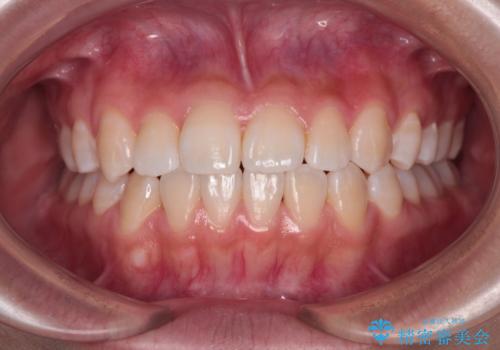

外側に飛び出した歯 インビザラインによる矯正治療

- 外に飛び出した側方の歯と、前歯のデコボコを気にして来院された患者様です。

IPR(歯と歯の間を削る)によってデコボコが解消するように設計し、インビザラインにより治療を行うこととしました。

治療途中で1年半以上通院されない時期があったため、後戻りが生じたことで治療期間が長くなってしまいました。

親知らずを抜去したことで、下顎のデコボコがきれいに解消されました。